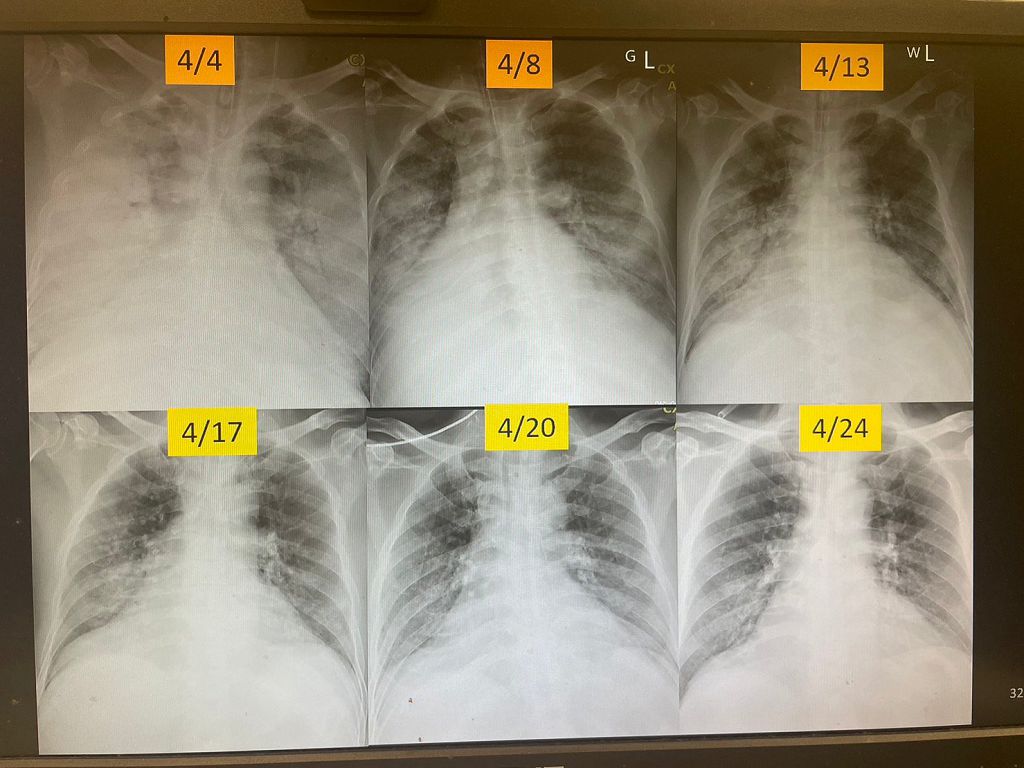

病患是清明節假期自北部返回玉里老家祭祖,蘇桂英主任指出,病人的上呼吸道症狀經診所醫治並未好轉,且連續四天出現咳血症狀,被家人送往鄰近醫院治療,因病情嚴重再被轉送花蓮慈院急診。到院時,病人呼吸喘、咳血,胸部X光片顯示右邊肺部整片白掉,一開始懷疑肺部感染引起肺泡出血,急速惡化成急性呼吸窘迫症候群,立即轉送加護病房插管治療。

加護病房團隊警覺性的先投以抗生素治療。並因病人有花東旅遊史,醫療團隊也針對恙蟲病、及其他非典型肺部感染症進行檢驗,但病患插管後使用呼吸器支持,血中氧氣量仍偏低。蘇桂英主任說,這是屬於死亡率40%-70%的急性呼吸窘迫症候群,且兩側肺葉持續白化,後續的肺部血管的電腦斷層檢驗找不到血管瘤破裂跡象也無法進行血管栓塞,肺部電腦斷層也排除了支氣管擴張症或癌症等肺部結構性病變,病患痰液的病毒培養、細菌檢查、包括肺結核菌檢查、透過支氣管鏡檢查的檢體經化驗都沒發現病原菌感染。

人體全身都有血管,包括肺部、腎臟,因此血管炎很容易造成腎臟急性惡化甚至洗腎,蘇桂英主任說,這位病人的症狀是以肺部出血為主,還好腎臟指數沒異常。嚴重肺部出血的病人死亡率超過5成,加護病房團隊很快的從病人各項檢查結果進一步做自體免疫疾病檢驗,才有正確治療方向,經過半個月的救治,病人已順利出院,由北部醫院接手續後續的照護處理;因有跨縣市、跨團隊的合作默契,才能讓病人得到最好的全人醫療照護。